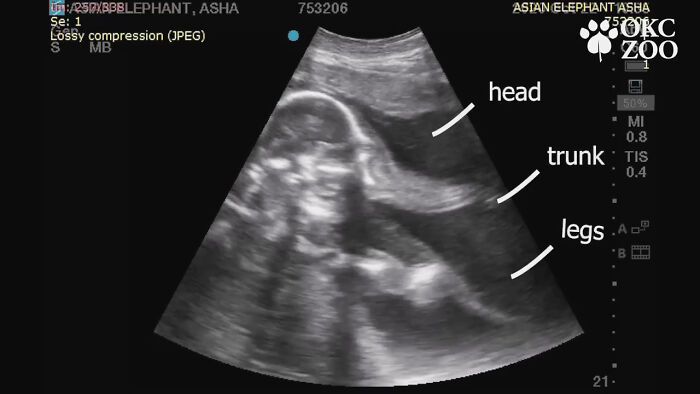

Pravidelnou metódou na kontrolu gravidity slona sú ultrazvuky, ktoré vykonáva veterinárny tím zoo. Posledný ultrazvuk – ten, ktorý je viditeľný aj vo videu nižšie – ukázal, že matka aj dieťa sú úplne zdravé. Na rozdiel od ultrazvukov vykonávaných na ľuďoch, ktoré sa častokrát veľmi ťažko rospoznávajú, je tento prekvapivo jasný. Hlava, chobot aj nohy sú veľmi ľahko a dobre viditeľné. A je to veľmi milé sledovať.